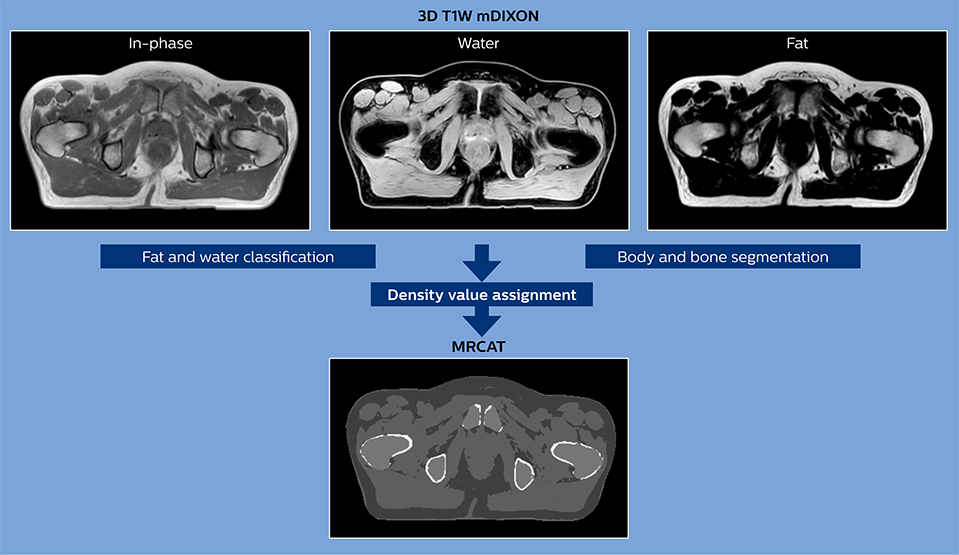

MR-only simulation workflow The 3D T1W FFE mDIXON sequence provides in-phase, water and fat images in one acquisition. Target and organs-at-risk are delineated on the 3D T2W TSE images. Prostate GTV is shown in orange, PTV in purple. The 3D bFFE sequence is used by the planner to mark the position of the fiducial markers (gold anchors) and contours are transferred to the digitally reconstructed radiographs (DRRs).

Based on the 3D T1W mDIXON images, MR-based density maps (MRCAT) are automatically generated. The VMAT (Volumetric Modulated Arc Therapy) plan is generated in TPS, based on MRCAT as primary image set. During the commissioning phase, dosimetric agreement between MRCAT-based and CT-based dose plans was studied and differences in the PTV dose were found to be minimal (<1% for most patients). Average difference in PTV mean values was 0.8% over the study group (n=62).

How does MRCAT generation work?

The Philips MRCAT approach for an MR-only based dose planning provides CT-like density information calculated from MR images for dose calculations, as well as high contrast anatomical T2W images for target delineation. [2-3] The MRCAT images with density information are DICOM conform and can be automatically exported to treatment planning systems (TPS) as primary image dataset for dose calculations and to generate MR-based digitally reconstructed radiographs (DRRs).

Electron density information is automatically generated on the MR console from a single T1W mDIXON MRI sequence in two steps: